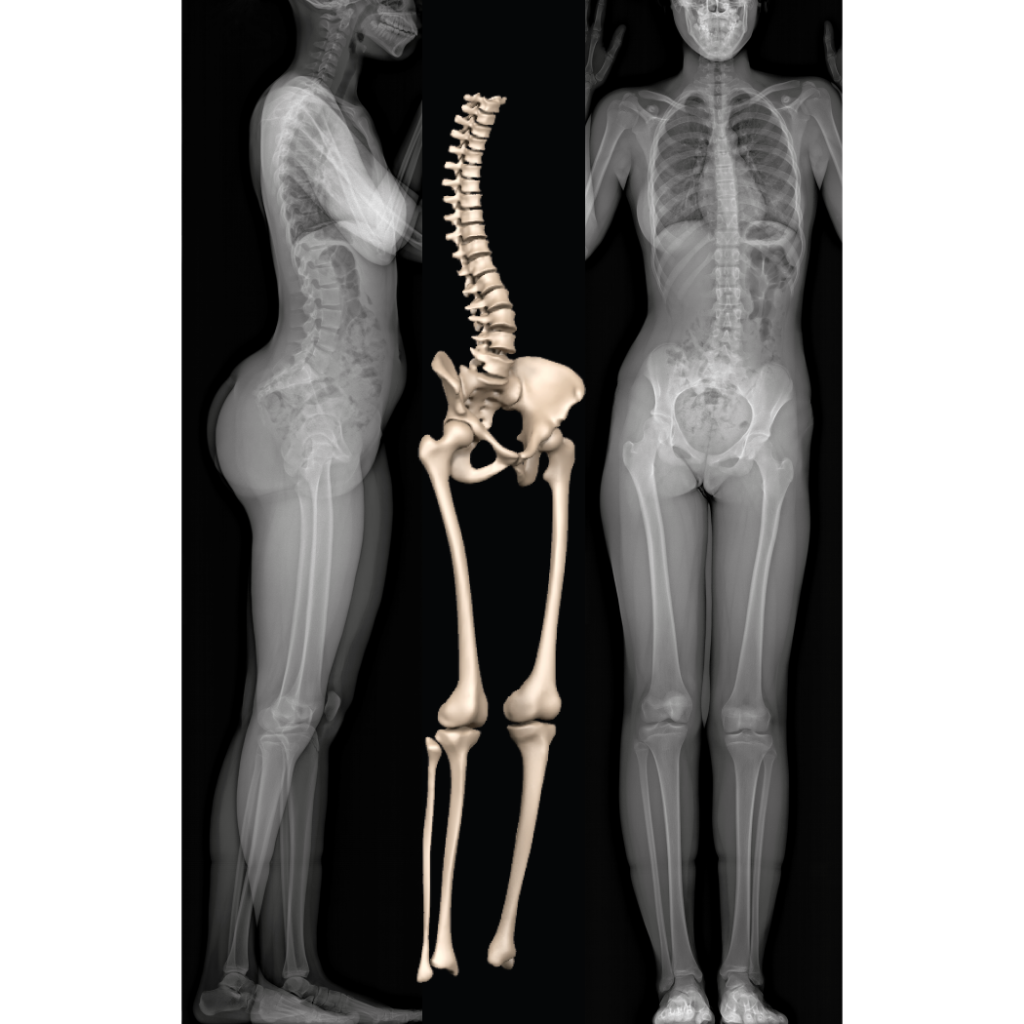

full body x ray pictures

EOSedge – EOS imaging

EOS System – EOS imaging

EOS Full Body Imaging – What Is It? | Restore Function Physiotherapy

Full Female Body X-Ray With Skeleton 3D model rigged | CGTrader

Full Female Body X-Ray With Skeleton 3D model rigged | CGTrader

Full Female Body X-Ray With Skeleton 3D model rigged | CGTrader